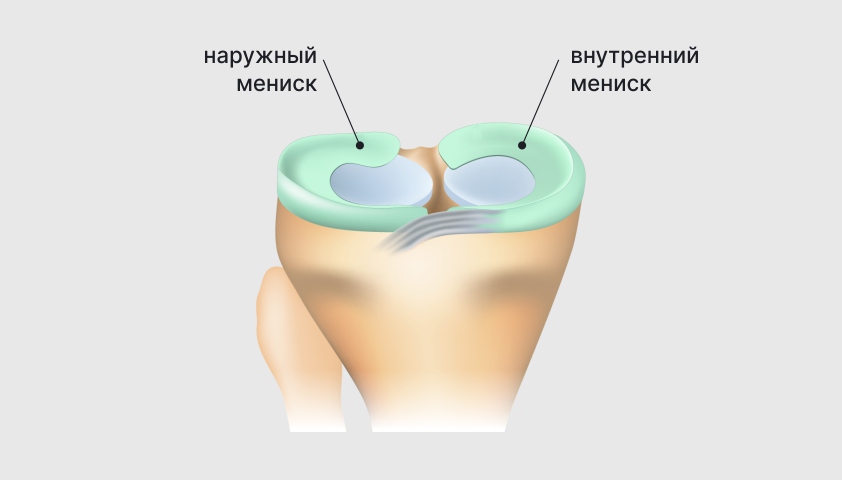

Заболевание сустава: симптомы и лечение